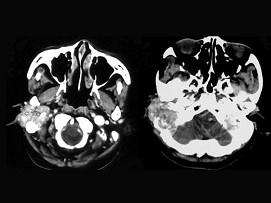

女,56岁,右侧中耳术后发现右外耳道新生物一年,PE:右外耳道内段被新生物充满,CT如图所示,应诊断为 ( )